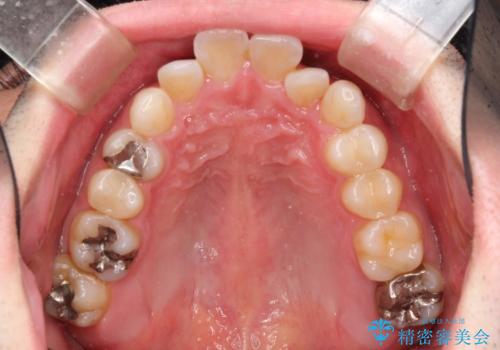

フルリンガル矯正 非抜歯でガタつきを整える

- フルリンガルワイヤーによる非抜歯治療を計画しました。

フルリンガルは違和感も強く操作も煩雑になるため、あまりおすすめはしていませんが、お仕事の都合などでどうしても装置を付けられない&マウスピースを管理することができない、場合はやむなく選択することもあります。